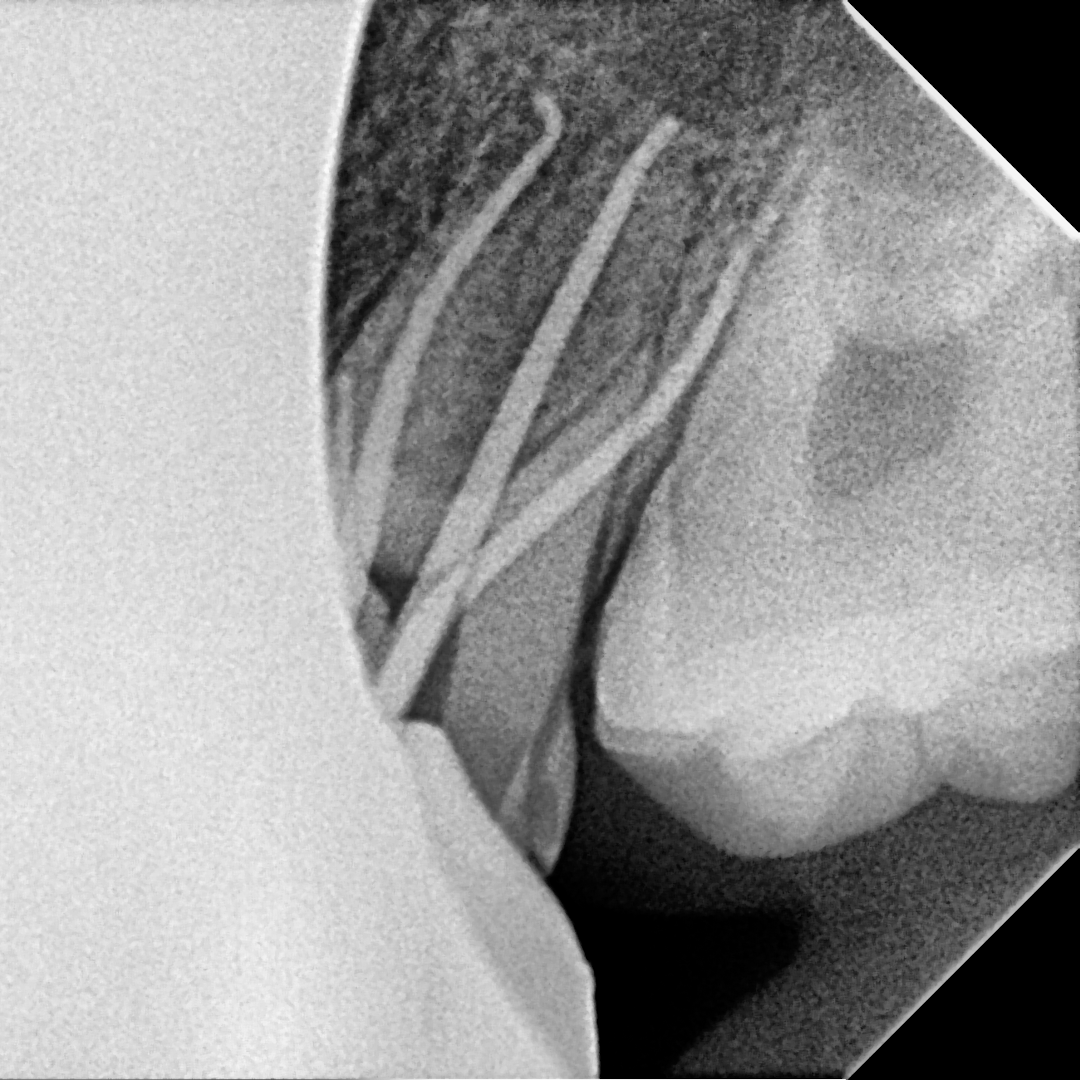

Endodontics upper 6 with MB3